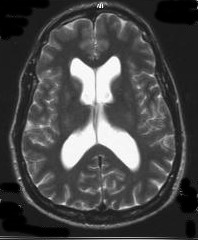

CT Image 6-28-2010, 17 days post slit ventricle finding (image/CD courtesy of Hoag Imaging Center)